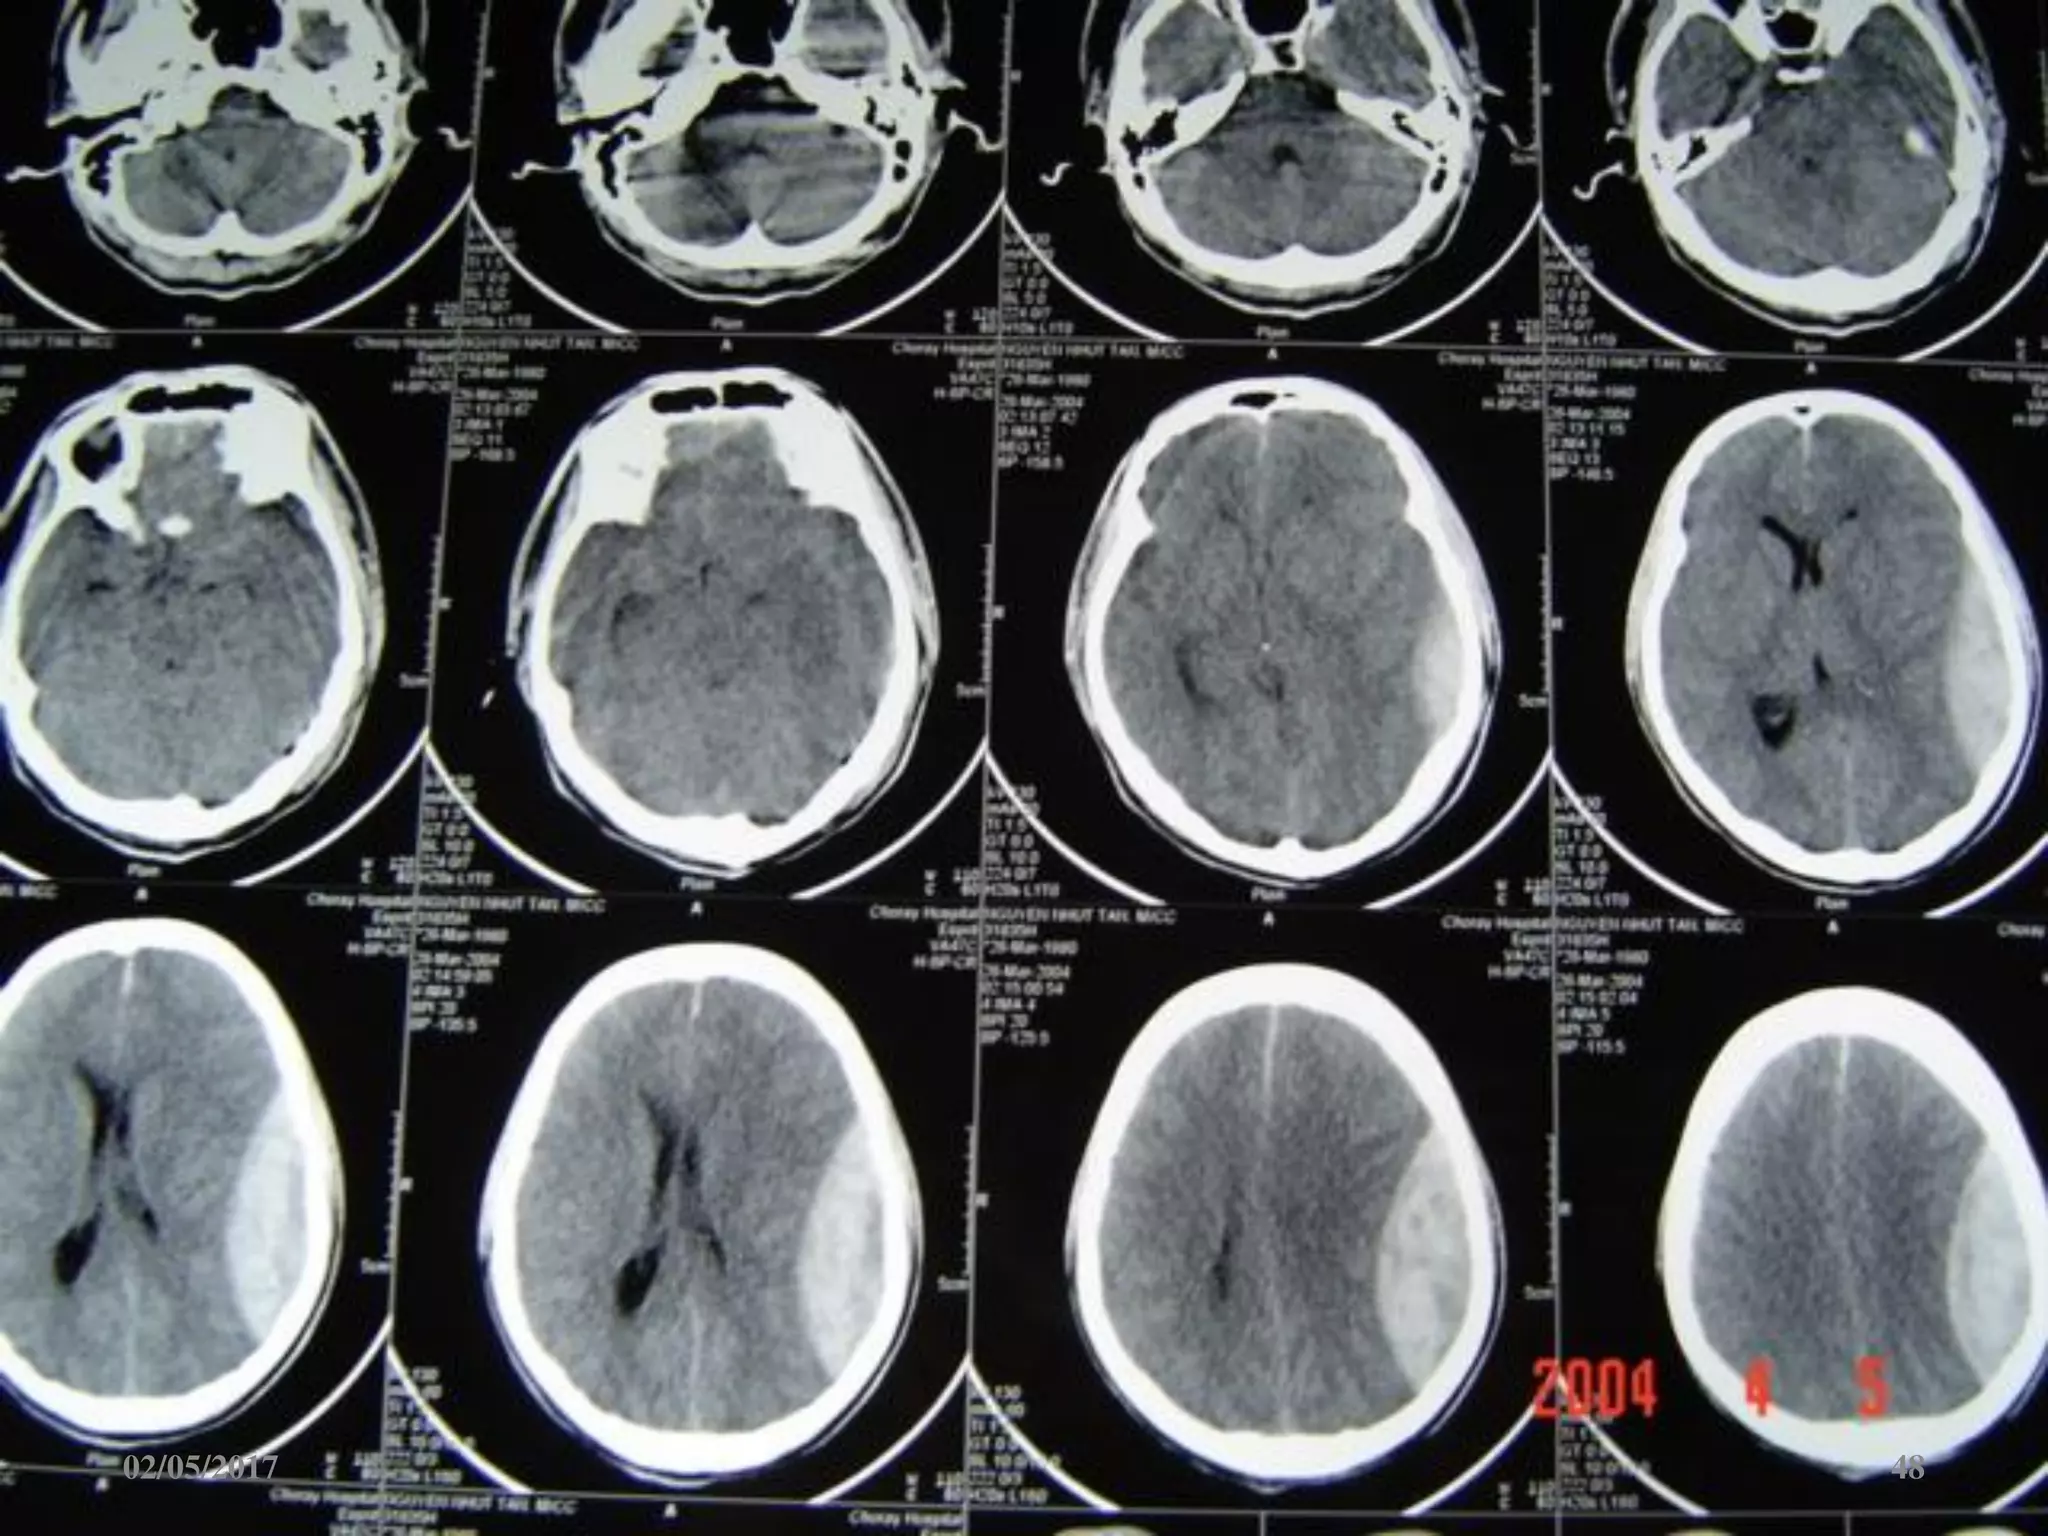

Máu tụ dưới màng cứng cấp

 Ngoài trục, hình liềm,

tăng đậm độ

 Vượt qua được các

khớp sọ

 Thường kèm dập não